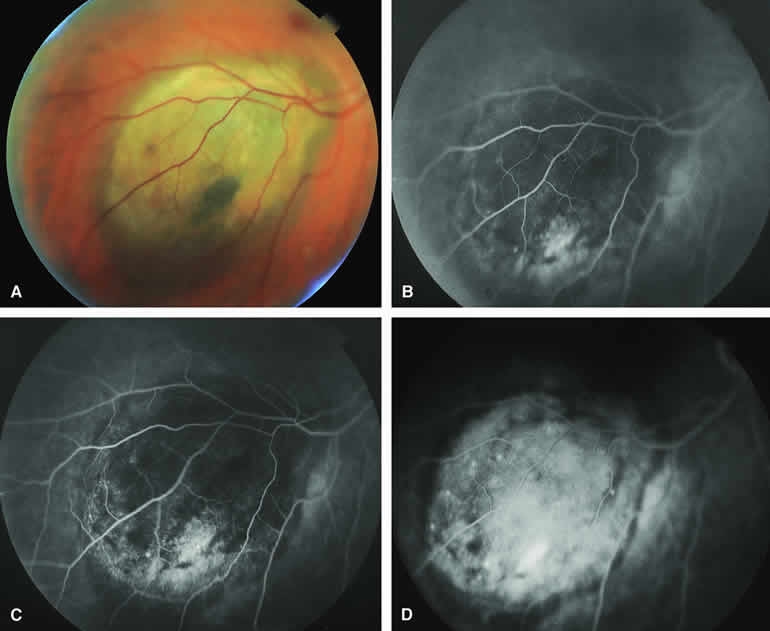

Typical Melanotic Choroidal Nevus

Fluorescein angiography of a typical choroidal nevus with bland surface features (see Fig. 1) shows the entire lesion to be hypofluorescent relative to the adjacent uninvolved choroid throughout the study. No large-caliber choroidal blood vessels are usually identifiable within the lesion. The retinal vasculature overlying the lesion appears well defined and normal on fluorescein angiography.